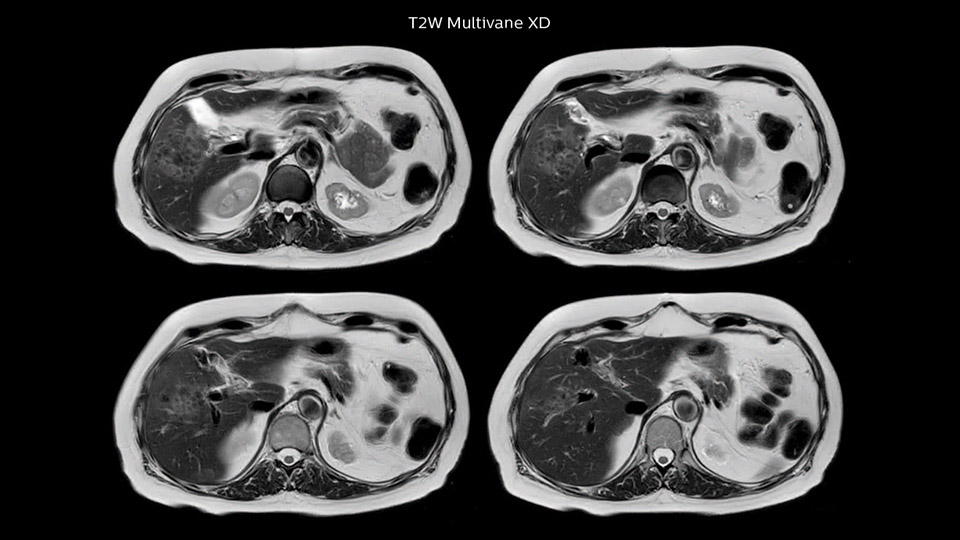

Comparison of liver MRI with and without MultiVane XD motion correction

In this example the image quality of the MultiVane XD images is evidently better than in the images without MultiVane XD. Ingenia 1.5T with dS Torso coil solution.

“We acquire one transversal high resolution T2-weighted sequence with 3 mm slice thickness, for example for pancreas or liver lesions. Then we also add a T2 fat suppressed MultiVane XD SPIR sequence. We perform these two routinely in our liver imaging. We use high dS SENSE factors to significantly shorten scan times to 2-4 minutes, which can improve our protocol; it’s a very robust scan.”

“I would absolutely recommend to other sites to implement MultiVane XD with dS SENSE in their abdominal cases, as it’s brilliant for robust, motion-corrected abdominal imaging. It provides us with excellent image quality with high resolution in a short time,” says Dr. Baumann. “I would advise using MultiVane XD for T2 and T2 fat suppressed high quality imaging for almost every liver case.”